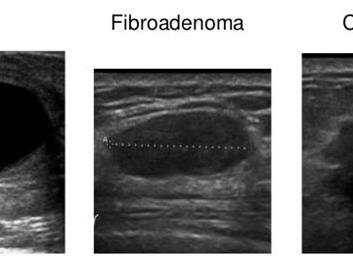

Как выглядит фиброаденома на УЗИ

Для фиброаденомы, выявляемой на УЗИ, присущи следующие характеристики:

• новообразование объемное и визуализируется, как округлое, овальное, дольчатое;

• гомогенное образование однородно по своей структуре;

• чередование участков различной эхогенности;

• присутствует тонкий эхогенный ободок с выраженным задним акустическим усилением.

Среди атипичных признаков также может отмечаться микродольчатость, неровные края и присутствие акустической тени. Тип фиброаденомы будет сказываться на виузализации новообразования: